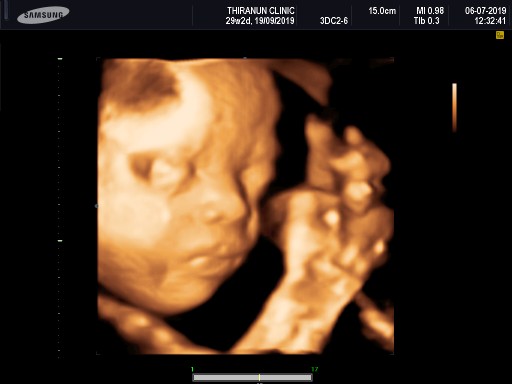

29 วีคค่ะ